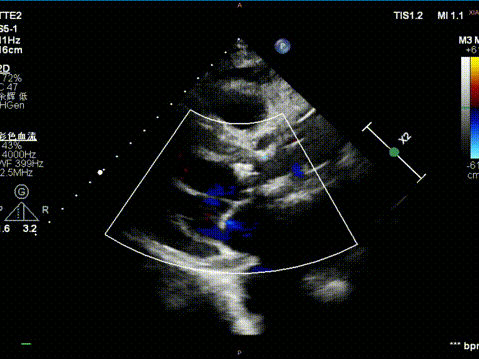

患者为70岁男性,心脏彩超显示左房、右房增大,主动脉瓣增厚、钙化,重度狭窄并轻度关闭不全(Vmax 587cm/s,MaxPG 138mmHg,MeanPG 67mmHg,有效瓣口面积0.66cm²),室间隔与左室后壁增厚,并合并轻度二尖瓣、三尖瓣反流。

术后超声

闭合血管入路,完成手术。本例难点在于SAVR术后结构性瓣膜衰败导致主动脉瓣反流,原外科瓣膜未见钙化,术前经充分沟通,确定植入深度于瓣架第一节点与第二节点间,保证瓣架底部在外科瓣膜环上具有足够锚定力。术中,瓣架完全释放前小弯侧深度稍大于大弯侧,微量PVL,在最终时提示术者对递送系统轻微施加推力,释放后两侧深度达到平衡,PVL消失,平均压差2mmHg,舒张压即刻恢复正常。